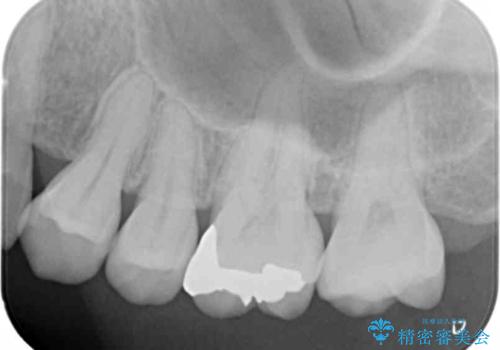

定期的にX線写真を撮影しチェックすることで、外から見てわかるプラークコントロールだけでなく虫歯を初期段階で発見し対策することができます。

歯ぎしりの癖があることから強度に優れるゴールドインレーにて修復を行いました。

- 7.7万円 (ゴールドインレー)費用は治療当時の料金となります

ゴールドは強度に優れ、適合も良い修復物を製作することができます。